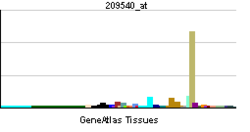

IGF-1 is produced primarily by the liver. Production is stimulated by growth hormone (GH). Most of IGF-1 is bound to one of 6 binding proteins (IGF-BP). IGFBP-1 is regulated by insulin. IGF-1 is produced throughout life; the highest rates of IGF-1 production occur during the pubertal growth spurt.[12] The lowest levels occur in infancy and old age.[13][14]

The polypeptide hormone IGF-1 is synthesized primarily in the liver upon stimulation by growth hormone (GH). It is a key mediator of anabolic activities in numerous tissues and cells, such as growth hormone-stimulated growth, metabolism and protein translation.[17] Due to its participation in the GH-IGF-1 axis it contributes among other things to the maintenance of muscle strength, muscle mass, development of the skeleton and is a key factor in brain, eye and lung development during fetal development.[18]

The levels of IGF-1 in the body vary throughout life, depending on age, where peaks of the hormone is generally observed during puberty and the postnatal period. After puberty, when entering the third decade of life, there is a rapid decrease in IGF-1 levels due to the actions of GH. Between the third and eighth decade of life, the IGF-1 levels decrease gradually, but unrelated to functional decline.[18] However, protein intake is proven to increase IGF-1 levels.[20]